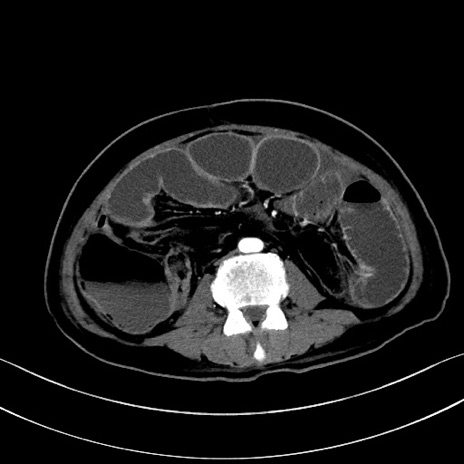

症例28(横断像)

【症例】60歳代男性

【主訴】嘔吐

【現病歴】胃癌にて胃全摘後。食思不振が悪化し、夜中に嘔吐することがある。

【既往歴】胃癌、胃全摘、脾摘、胆摘後

【データ】WBC 5900、CRP 10.56